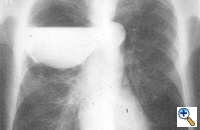

The preoperative work-up should always include clinical and functional evaluation (arterial blood gas analysis and pulmonary function tests with plethysmography), chest x-ray (Figure 6), computed tomography (Figure 7), and V/Q scan (Figure 8). Pulmonary angiography (Figure 9) has been reported to show some advantages in evaluating the underlying lung; however, it is not routinely performed.